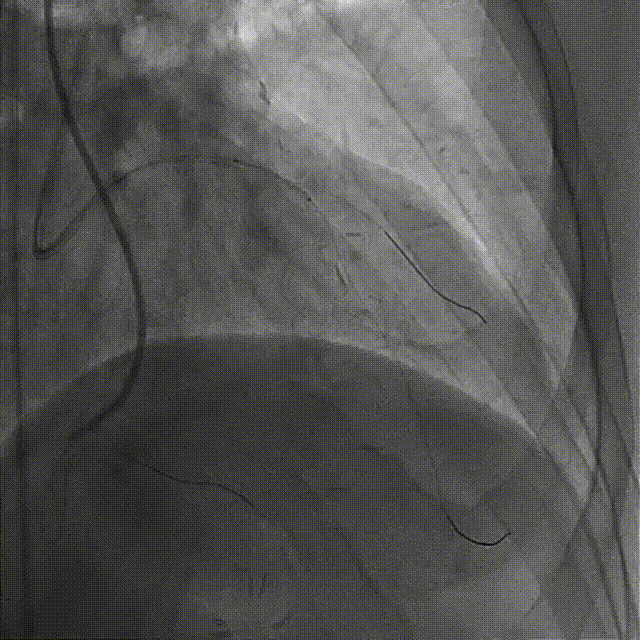

置7F UBS 3.75、6F JR 4.0指引导管至左右冠开口,分别送入Marvel导丝至LCX远段、RCA远端加强支撑,行双侧造影。

在微导管支撑下,Sion导丝无法经OM1心外膜侧枝逆向至LAD远段,改送Fielder XT-R导丝逆向至LAD远段。

HighTrack微导管跟进至闭塞病变远端,正向工作导丝做指引,应用Fielder XT-A导丝逆向通过闭塞段至LM内,反复尝试调整导丝未能进入正向指引导管。